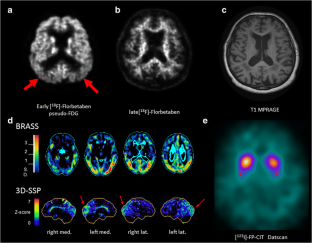

Hsiao I-T, Huang C-C, Hsieh C-J, Hsu W-C, Wey S-P, Yen T-C, et al. Correlation of early-phase 18F-florbetapir (AV-45/Amyvid) PET images to FDG images: preliminary studies. Eur J Nucl Med Mol Imaging. 2012;39:613–20.

- 41.

Jones DT, Machulda MM, Vemuri P, McDade EM, Zeng G, Senjem ML, et al. Age-related changes in the default mode network are more advanced in Alzheimer disease. Neurology. 2011;77:1524–31.

- 42.

Sheline YI, Raichle ME, Snyder AZ, Morris JC, Head D, Wang S, et al. Amyloid plaques disrupt resting state default mode network connectivity in cognitively normal elderly. Biol Psychiatry. 2010;67:584–7.

- 43.

Myers N, Pasquini L, Göttler J, Grimmer T, Koch K, Ortner M, et al. Within-patient correspondence of amyloid-β and intrinsic network connectivity in Alzheimer’s disease. Brain J Neurol. 2014;137:2052–64.

- 44.

Griffa A, Baumann PS, Thiran J-P, Hagmann P. Structural connectomics in brain diseases. Neuroimage. 2013;80:515–26.

- 45.

Alsop DC, Dai W, Grossman M, Detre JA. Arterial spin labeling blood flow MRI: its role in the early characterization of Alzheimer’s disease. J Alzheimers Dis. 2010;20:871–80.

- 46.

Kendziorra K, Wolf H, Meyer PM, Barthel H, Hesse S, Becker GA, et al. Decreased cerebral α4β2* nicotinic acetylcholine receptor availability in patients with mild cognitive impairment and Alzheimer’s disease assessed with positron emission tomography. Eur J Nucl Med Mol Imaging. 2011;38:515–25.

- 47.

Meyer PM, Strecker K, Kendziorra K, Becker G, Hesse S, Woelpl D, et al. Reduced alpha4beta2*-nicotinic acetylcholine receptor binding and its relationship to mild cognitive and depressive symptoms in Parkinson disease. Arch Gen Psychiatry. 2009;66:866–77.

- 48.

Jagust W. Time for tau. Brain. 2014;137:1570–1.

- 49.

Bailey DL, Barthel H, Beuthin-Baumann B, Beyer T, Bisdas S, Boellaard R, et al. Combined PET/MR: Where are we now? Summary report of the second international workshop on PET/MR imaging April 8-12, 2013, Tubingen, Germany. Mol Imaging Biol. 2014;16:295–310

- 50.

Garibotto V, Heinzer S, Vulliemoz S, Guignard R, Wissmeyer M, Seeck M, et al. Clinical applications of hybrid PET/MRI in neuroimaging. Clin Nucl Med. 2013;38:e13–8.

- 51.

Drzezga A, Barthel H, Minoshima S, Sabri O. Potential clinical applications of PET/MR imaging in neurodegenerative diseases. J Nucl Med. 2014;55 Suppl 2;47S–57S.